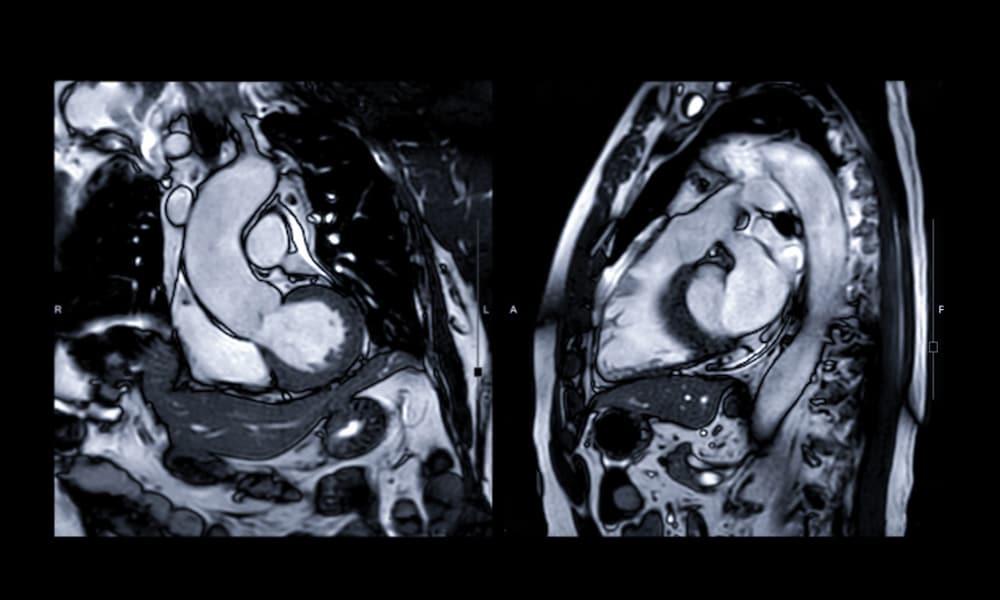

Imagerie Cardio-vasculaire

IRM 1.5 T Dernière Génération

Comment se déroule une IRM ?

L’imagerie par résonance magnétique (ou IRM) est un examen basé sur l’utilisation de champs électromagnétiques. Il donne des images du corps en deux ou trois dimensions. Pour bien vous y préparer et faciliter son déroulement, voici quelques conseils.